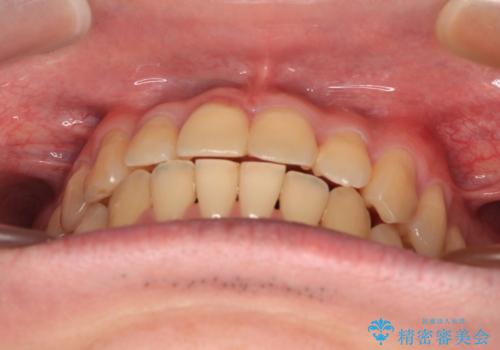

- 前歯のデコボコとクロスバイトを気にして来院された患者様です。

インビザラインでもワイヤー装置でも矯正治療は可能でしたが、煩わしい自己管理なしに短期間で治療を行いたいとのことで、目立たないワイヤー装置にて治療を行うこととしました。

- 30代男性

- 1年1ヶ月